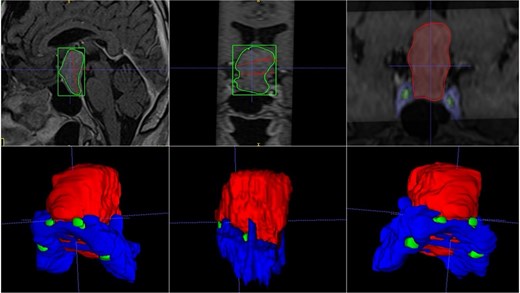

A 42-year-old male patient presented with a history of difficulty seeing in both temporal fields. The examination confirmed said bitemporal hemianopsia. We observed a sellar lesion in the MRI (T1, T2, and T1 sequences with contrast). With the segmentation, we were able to almost reconstruct the cavernous sinus and the internal carotid artery wholly in its intracavernous and clinoid portion and thus take more caution in the most rostral and dorsal region of the tumor since it was the site where both clinoid carotid arteries were closest each other (Fig. 7).

MRI and 3D volumetric segmentation of pituitary macroadenoma. Note the proximity of the internal carotid artery (green) in the most rostral and dorsal region of the tumor (red). Cavernous sinus (blue).